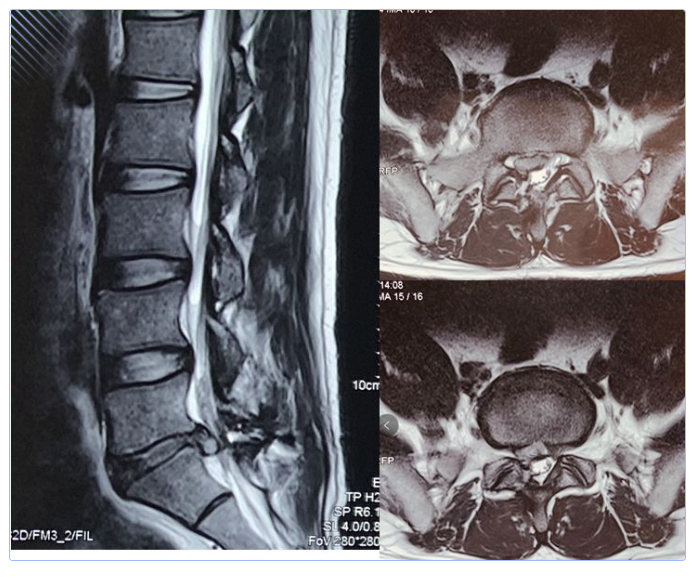

何教授听完了姜先生曲折的求诊经历后,为他感到揪心,也非常重视。立即为他安排了住院治疗,并且完善了相关检查。检查后CT发现,姜先生的腰5骶1右侧有巨大型突出,严重压迫了右侧神经根。

MRI检查更证实了姜先生的腰5骶1有巨大型椎间盘脱出,偏下偏右,压迫了椎管及右侧神经根。